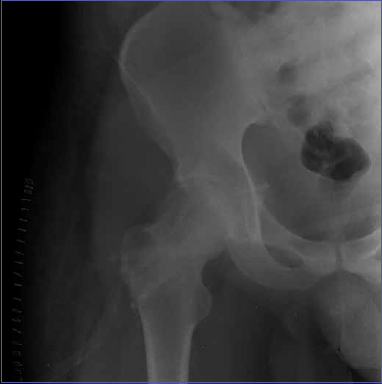

This case involves a 28-year-old male presenting with progressive right hip pain. Radiological investigations (contrast-enhanced magnetic resonance imaging [MRI] and computed tomography [CT]) and biopsy confirmed the diagnosis of GCT in the femoral neck and head. No signs of metastases or soft tissue involvement were detected (Figs. 1-3).

Figure 3.RIGHT HIP RX.